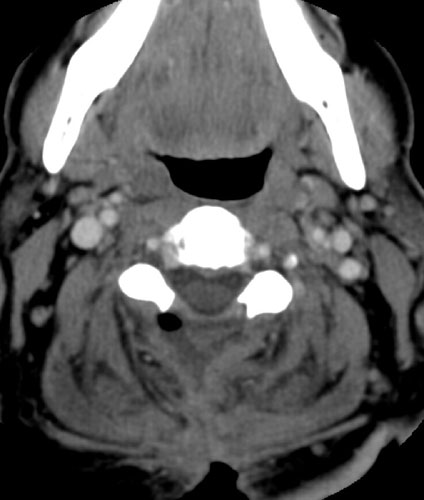

| Contrast enhanced axial CT scan demonstrates unroofing

of the spinal canal from the C2 to the C7 with bilateral laminectomies and

removal of the spinous processes. There is a fluid collection without

significant rim enhancement in the post surgical bed at the C2 level,

posterior to the spinal canal. Within this, there is some air. The fluid

collection appears to extend inferiorly to the C3 level, and then a small

slit of fluid continues inferiorly to the C5 - 6 level (not shown), where it appears

to communicate with the midline incision . |